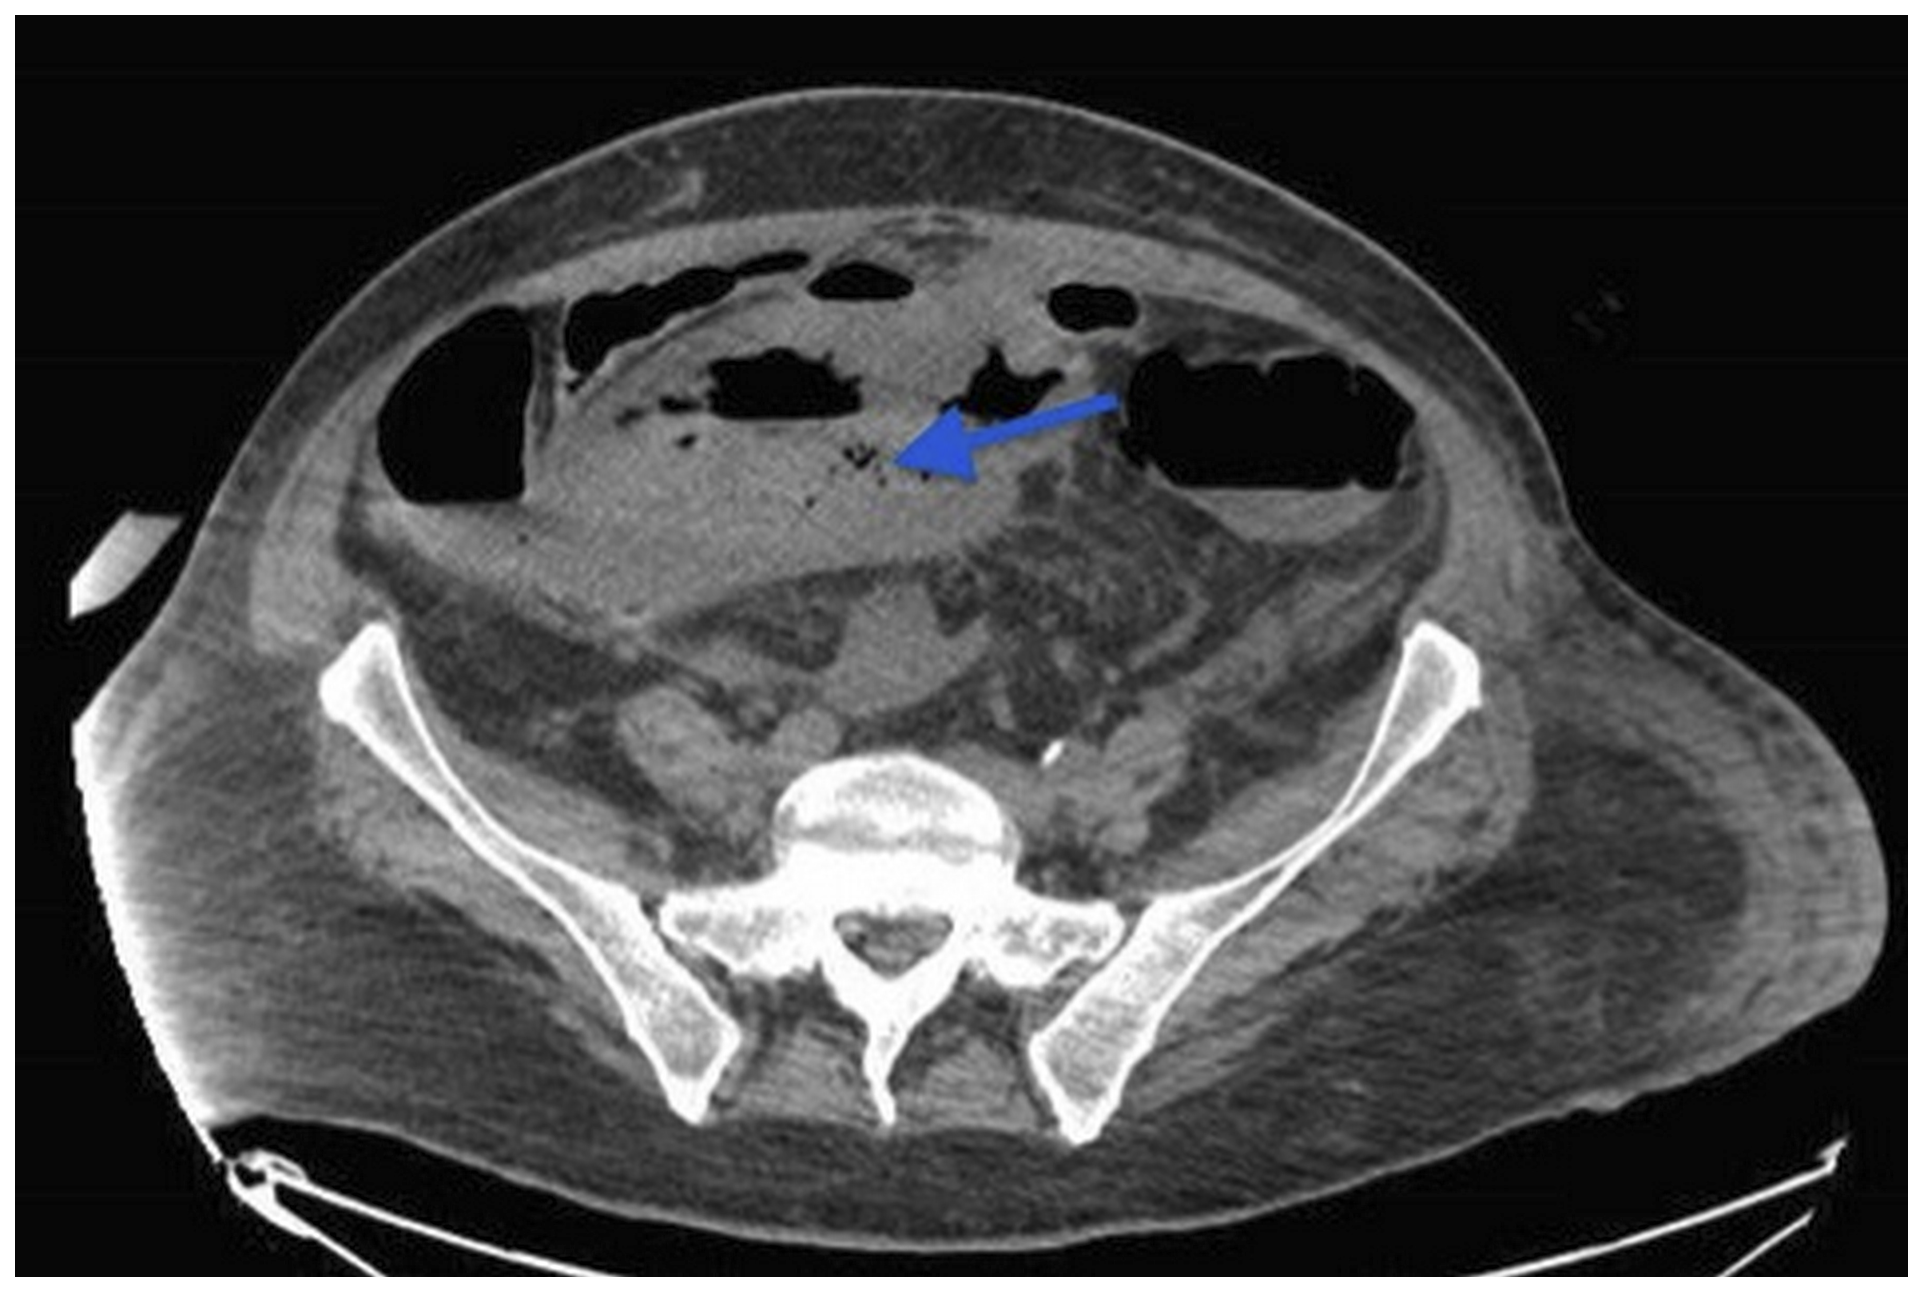

Eight days after the initiation of SUTENT (Sunitinib) 800 mg/day, and in front of the persistent fever and severe abdominal pain, a CT scan of the abdomen and pelvis was done and revealed the presence of gas inside the right inguinal mass due to fistulisation of an intestinal loop with localized peritonitis (Figure 2).

Figure 2: CT scan of the abdomen and pelvis revealed the presence of gas inside the pelvic mass (arrow) due to fistulisation of an intestinal loop with localized peritonitis.